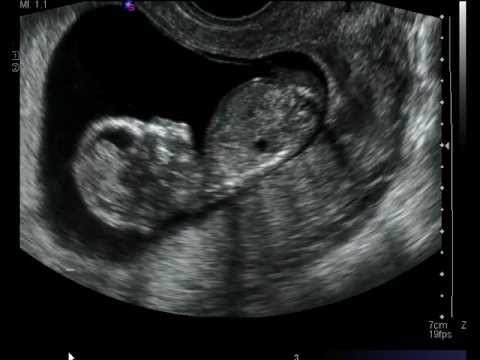

يمكن معرفة علامات الطفل المنغولي في السونار عن طريق فحص الشفافية القفوية للجنين، ويتم ذلك من خلال فحص الفقرات العنقية الخاصة به خلال الفترة بين الأسبوع 11 إلى الأسبوع 13 من الحمل.

ويركز هذا الفحص على مساحة صغيرة توجد بالنسيج الموجود بمؤخرة عنق الجنين والذي يطلق عليها اسم الطية القفوية، وقد كشفت الدراسات أن تلك البقعة تقوم بجمع السائل القفوي، وفي حالة إذا أظهرت النتيجة وجود كمية أكبر من السائل القفوي، فإن احتمالية اصابة الجنين بأمراض اختلال الكروموسومات مثل متلازمة داون تصبح أكبر.

يمكن لهذا الفحص أن يكشف عن العيوب الخلقية التي تكون مصاحبة لمتلازمة داون مثل: وجود عيب بالجدار الاذيني البطيني للقلب، أو وجود عيوب بالأمعاء الدقيقة، أو عدم وجود عظام الأنف، أو وجود قصر بعظم الفخذ.

لا تعد نتائج سونار الحمل دقيقة بالشكل الكافي، حيث إن قابليته في تحديد الاصابة بمتلازمة داون عن طريق فحص السائل القفوي تمثل 75% من الحالات، ويستطيع السونار أن يكشف حوالي 58% من حالات العيوب الخلقية المصاحبة لمتلازمة داون والتي من أبرزها غياب عظام الأنف.